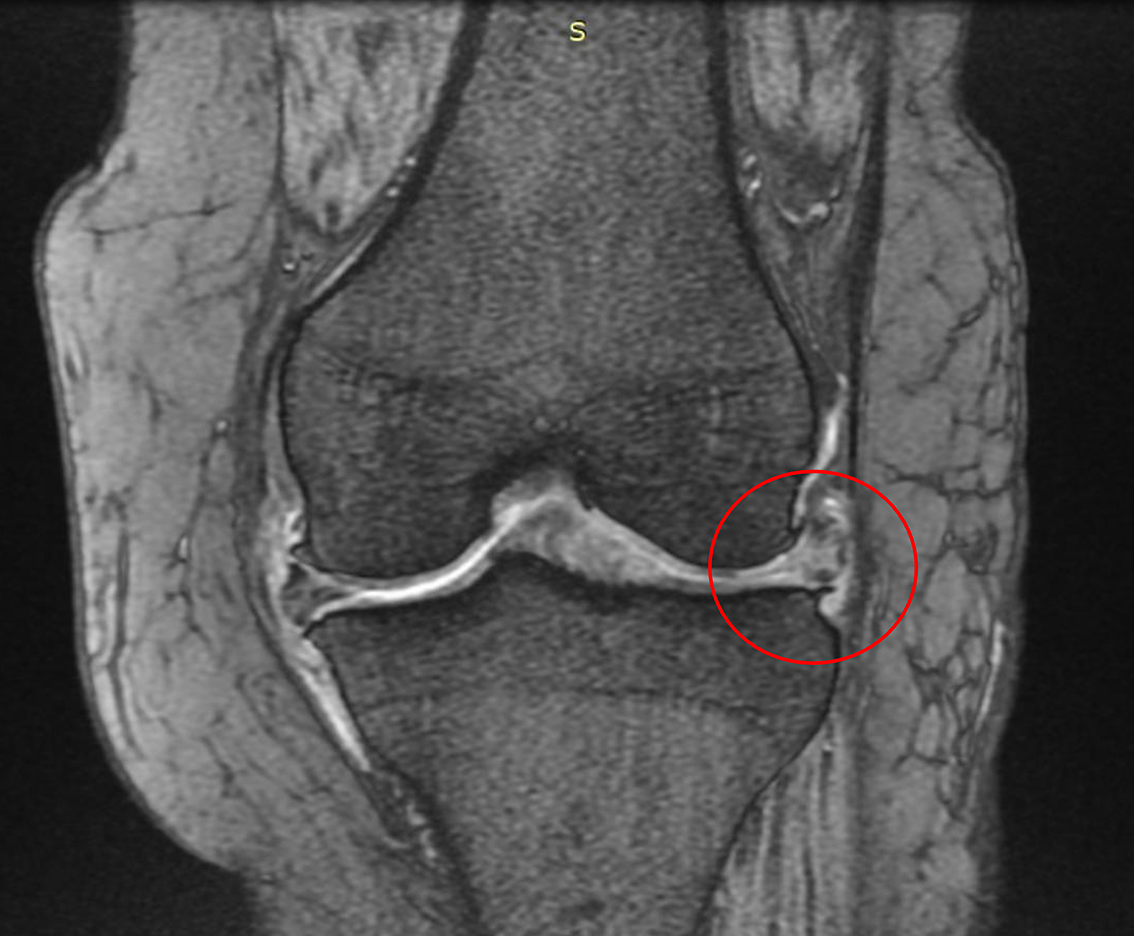

患者様は1年前から自覚症状が出始めた変形性膝関節症で、幹細胞治療による改善・根治を目的に当院にいらっしゃいました。痛みスコアは10段階のうち8(VAS 8/10)で、MRIでは変形性膝関節症のレベルは4段階で3(KL 分類3/4)に加え半月板の損傷もみられました。

所見:

- 膝関節に炎症(白っぽさ)が全体にある

- 内側の半月板に損傷(白い部分)

- 内側で関節が狭くなっている